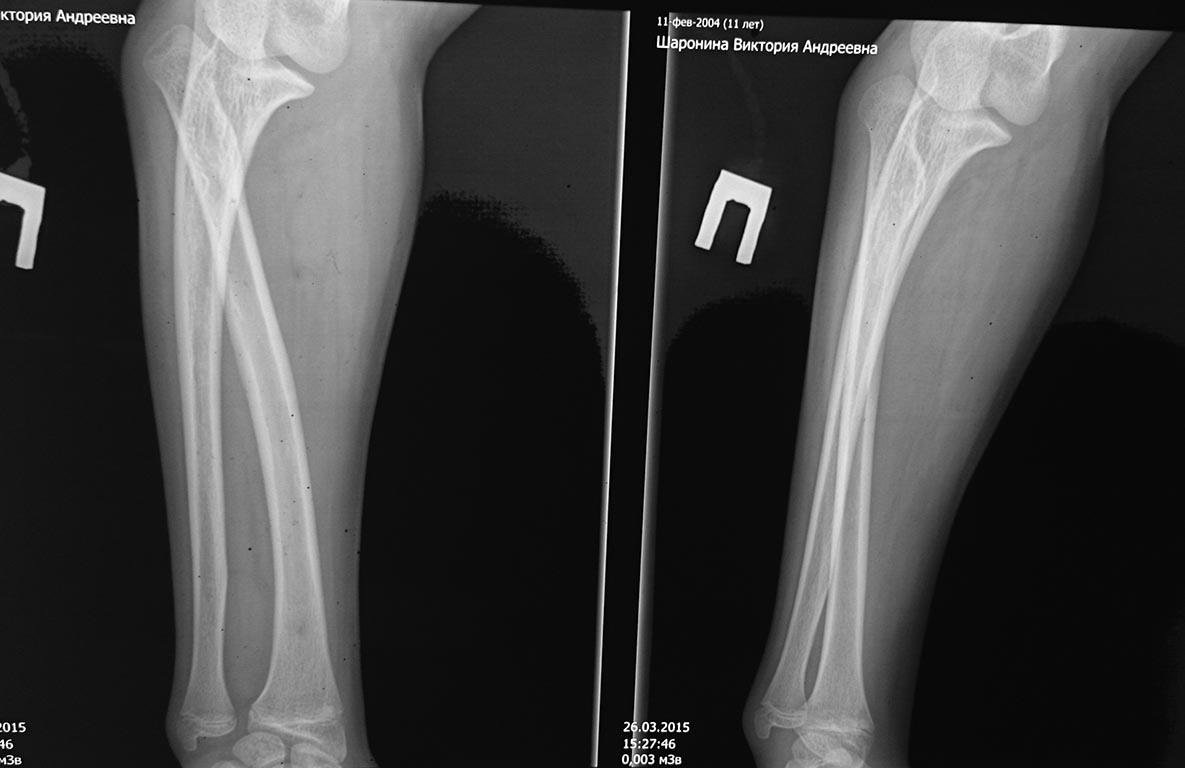

Для сравнения-рентген здоровой конечности

Кстати, все ли нормально по снимкам с дистальным луче-локтевым суставов?!

Может это мое субъективное мнение, но , если посмотреть первые и сравнительные снимки ниже,то и левый (здоровый) луче-плечевой сустав с признаками уплощения суставных поверхностей, но без вывиха головки. Видна также заметная разница в кривизне лучевых костей справа и слева. По поводу дистальных луче-локтевых суставов как по мне, то небольшая разница в суставной щели между ними есть. Разница в кривизне лучевых костей думаю связана с меньшим сопротивлением росту вывихнутого луча в условиях отсутствия точки опоры. В условиях функционирования удлиненный луч создает дисбаланс и в дистальном сочленении. Не думаю, что это существенно учитывая имеющиеся более серьезные проблемы